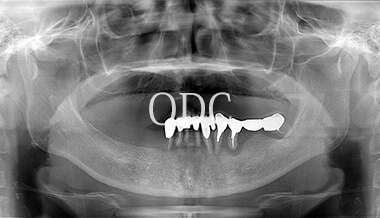

パノラマX線写真

術 前

術 後

術前・術後のパノラマX線写真です。上顎(オールオン4)は4本のインプラントにチタンフレームの上部構造が固定されているのがおわかりになると思います。下顎のインプラント埋入部位、上顎のインプラントの本数、再度写真をご覧いただくと、とてもインプラントが埋入されているとわからない程の外観、下顎の残存歯(元々の自分の歯)とも区別がつかない審美性が実現されています。